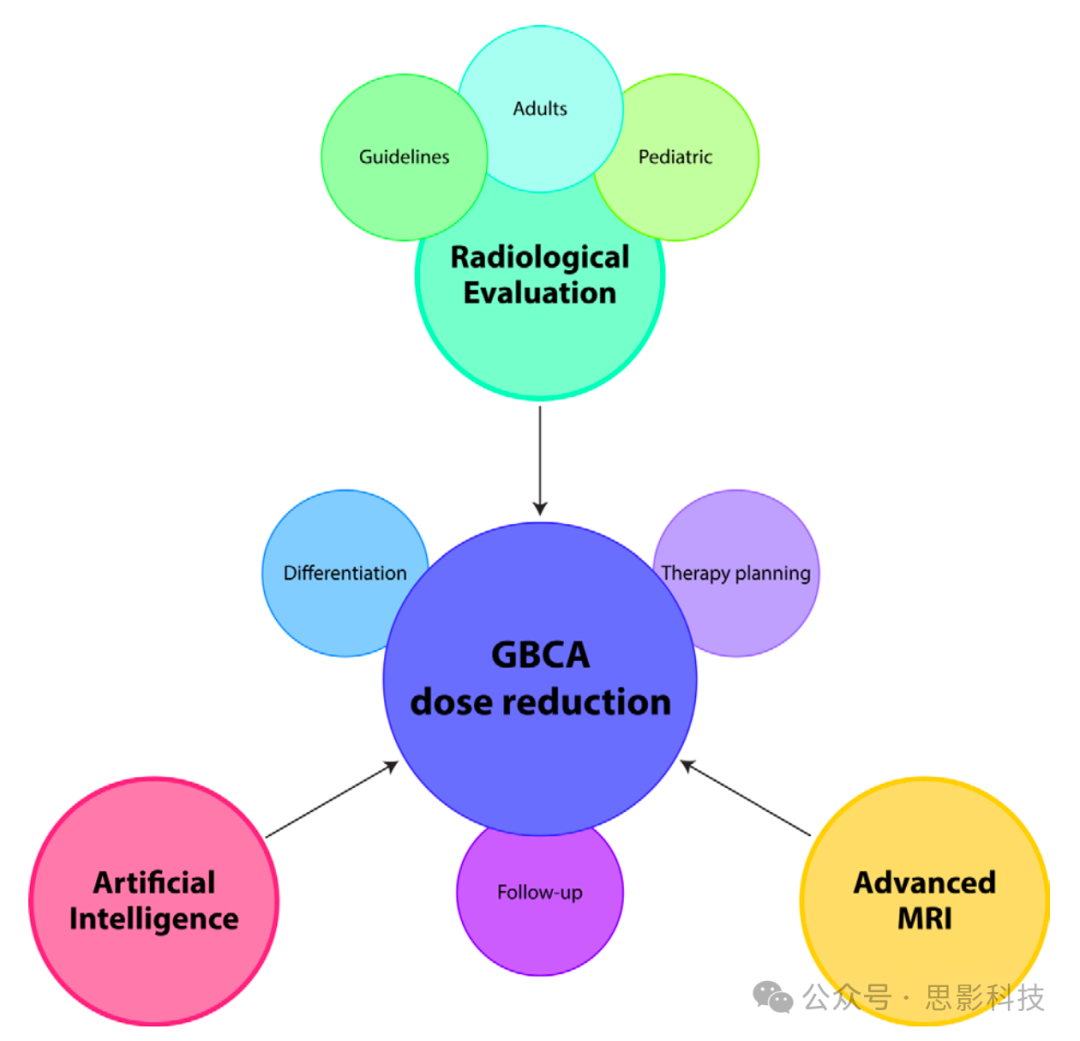

本文涵盖了在原发性脑肿瘤亚型分类、治疗计划和随访中减少GBCA暴露的替代图像采集和评估方法(图2)。审视了放射科医生和外科医生仅依赖无GBCA(或减量)图像的准确性,以及指南中关于GBCA使用和成像间隔的建议。我们还考虑了探测肿瘤生理特征和代谢的先进MRI技术,以及允许从无GBCA图像进行诊断预测和合成CE图像的人工智能应用。本文范围之外的是其他成像模式(如PET)以及需要GBCA给药的初始鉴别诊断考虑(如感染、炎症或脑转移)。胶质瘤和脑膜瘤是本综述的主要关注点。

图2:影像学评估实践(也在指南中表述)、无钆基造影剂(GBCA)的高级MRI序列以及人工智能是帮助减少GBCA在神经肿瘤学MRI诊断各个阶段使用的三大支柱。